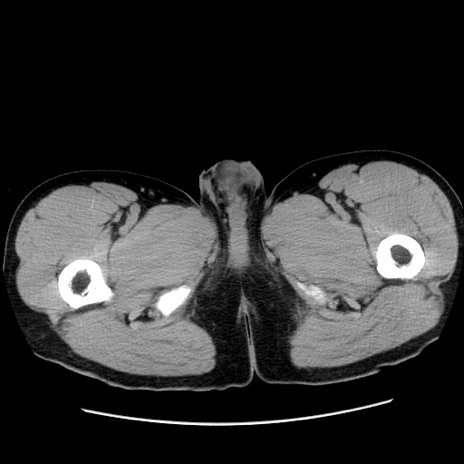

症例36(横断像)

【症例】20歳代 男性

【主訴】心窩部痛

【現病歴】今朝より上腹部痛あり。一旦軽快していたが再度出現したため救急要請。昨日夕に白身の魚を含む刺身を食べた。

【身体所見】BP 136/89mmHg、HR 74/min、BT 37.0℃、腹部:膨満、軟、心窩部に圧痛あり。反跳痛なし、筋性防御なし、腸雑音やや亢進あり。

【データ】WBC 17700、CRP 0.48